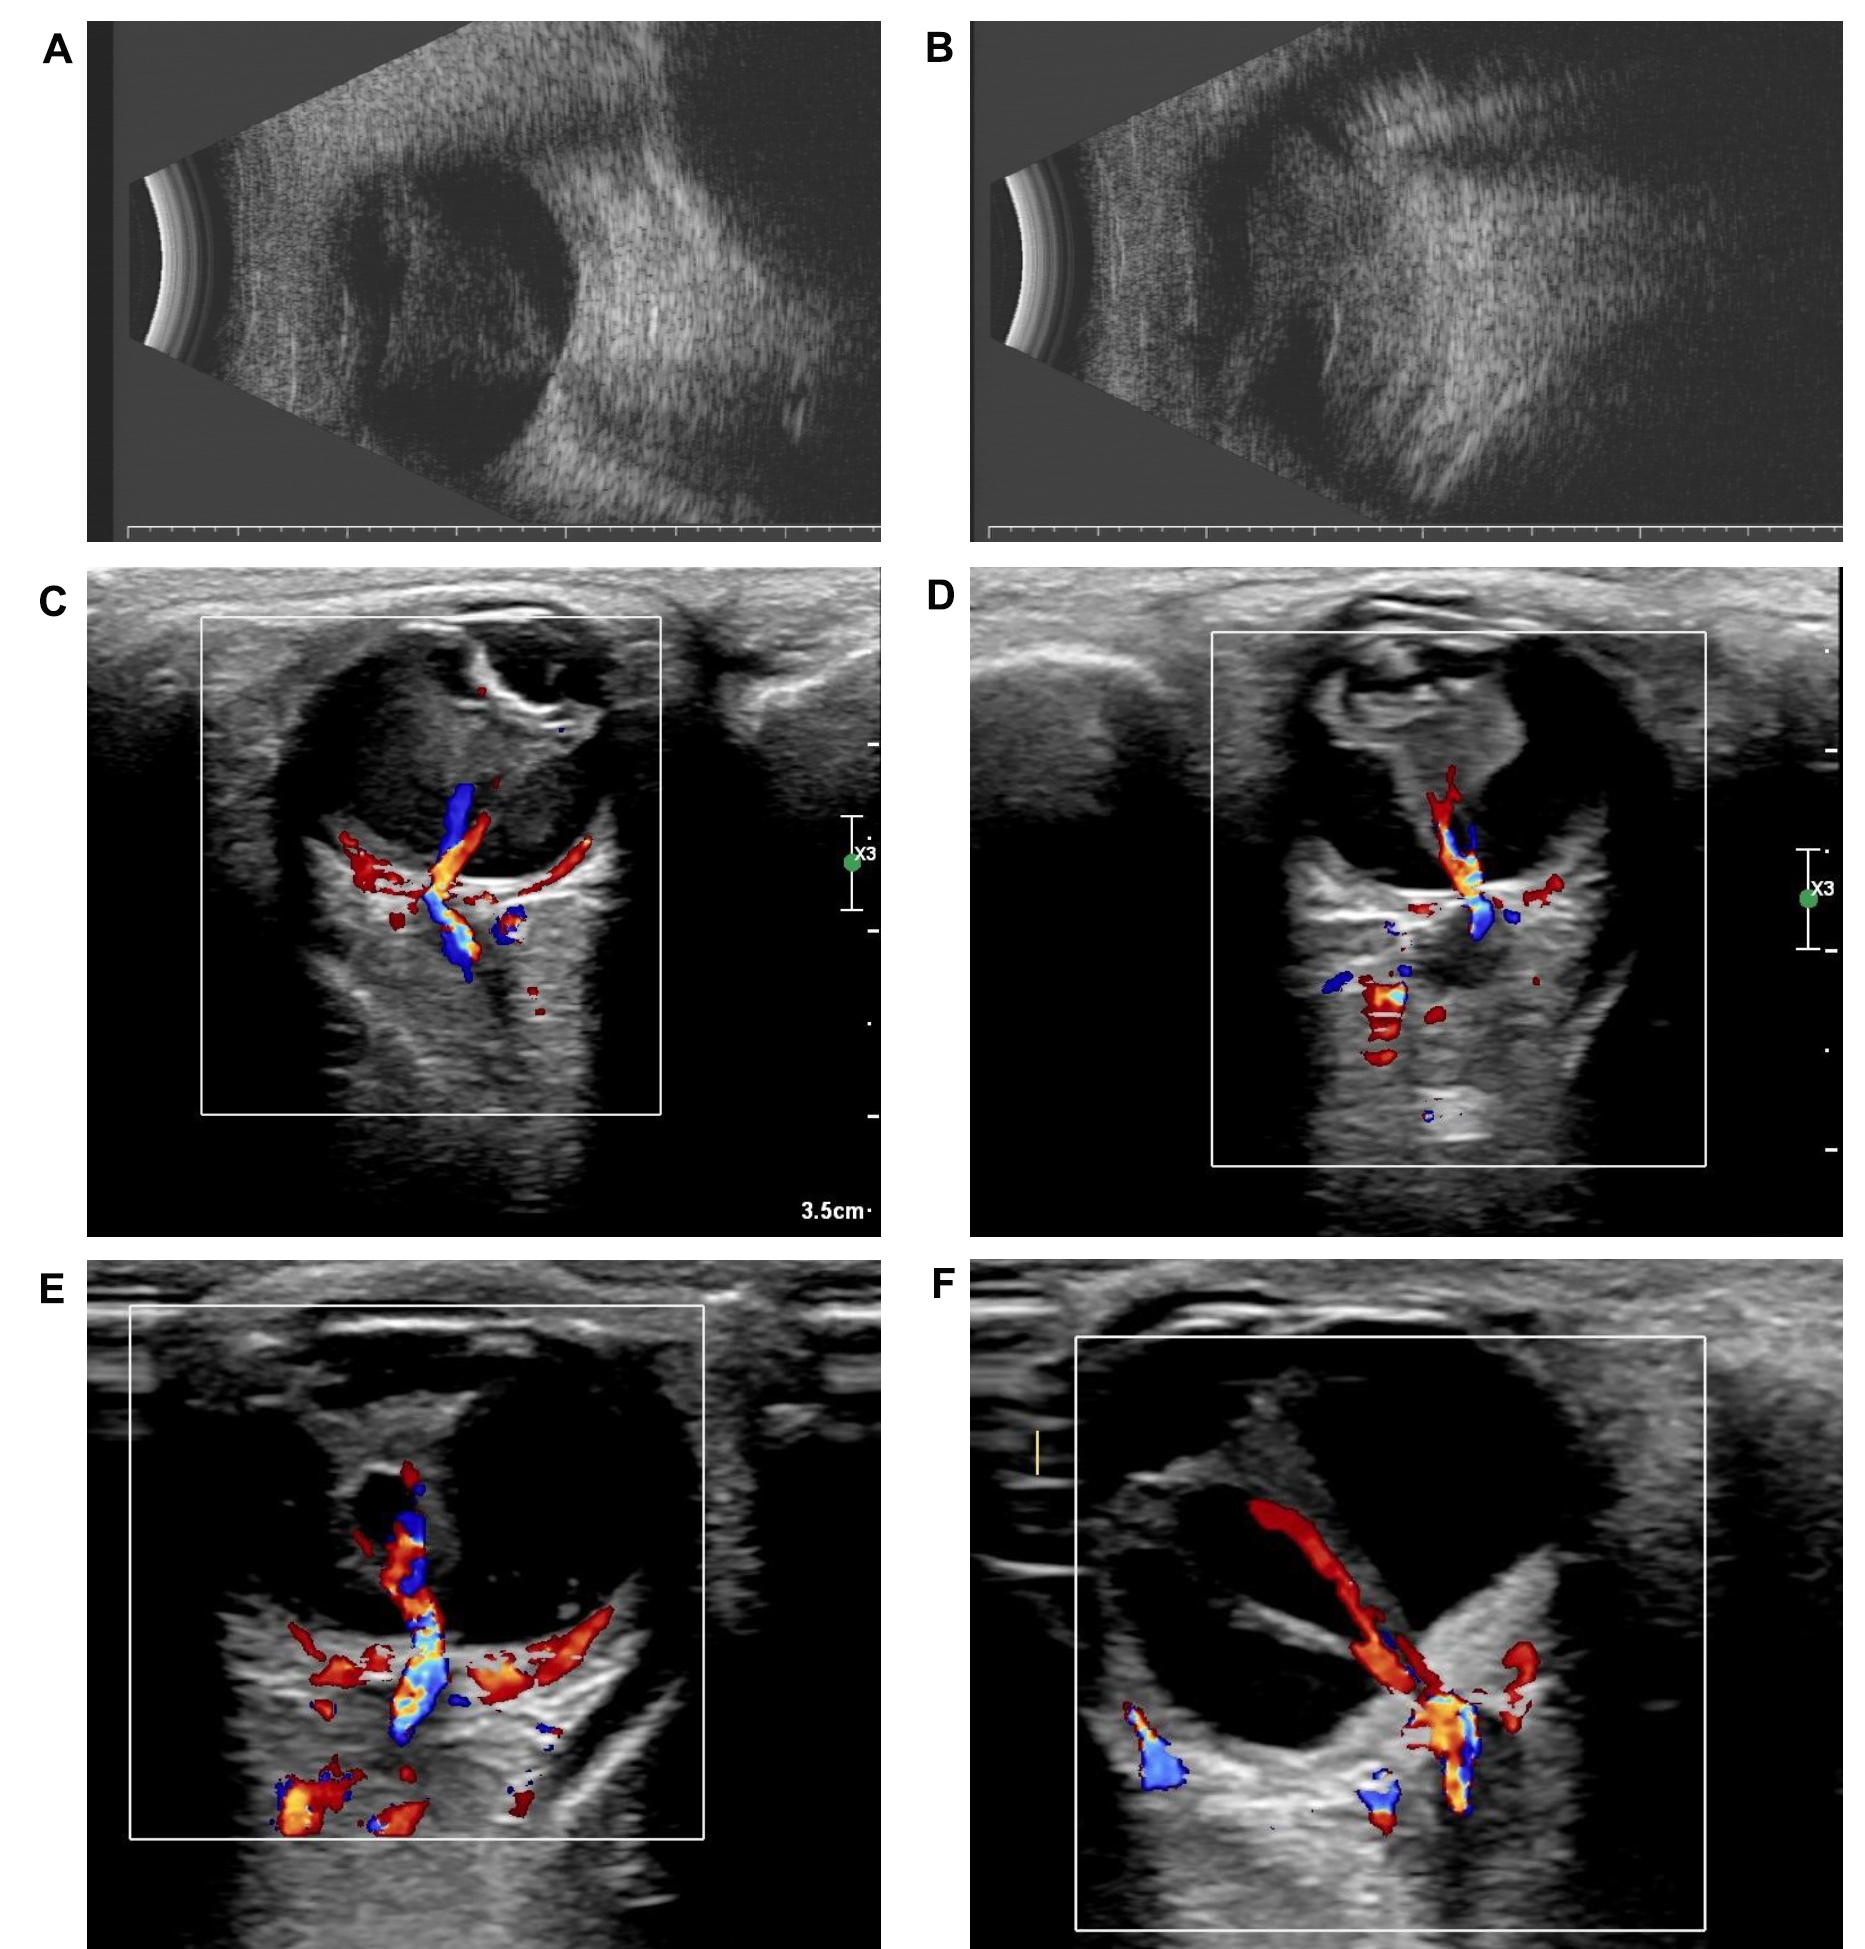

Figure 1.

Ultrasound of the three probands. Retinal detachment was detected in

A,B

: the right and left eyes of XDW1,

C,D

: the right and left eyes of DX1740, and

E,F

: the right and left eyes of DX1906.